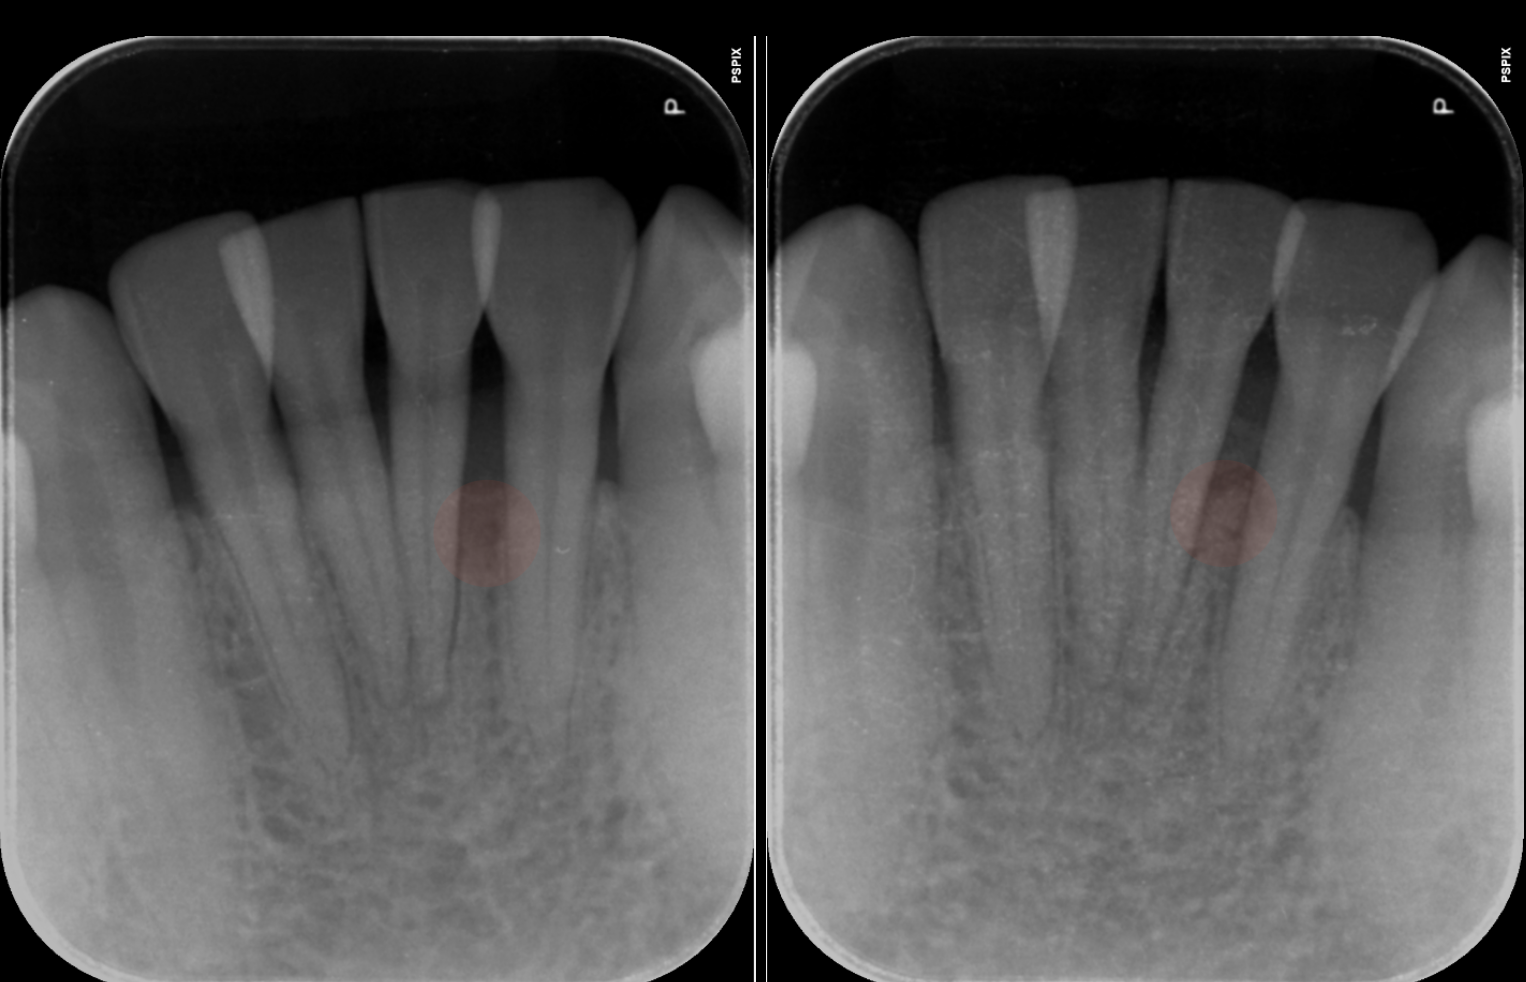

- 6.8 [20代男性]歯が折れた[歯の移植]